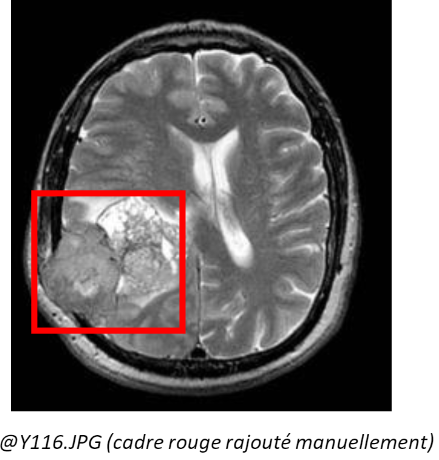

The data comes from a training set made available on Kaggle, more precisely at the following address: https://www.kaggle.com/datasets/navoneel/brain-mri-images-for-brain-tumor-detection There are 253 images available, mainly in .jpg format, although .jpeg and .png are also available. In these images, there are two categories, namely images showing a brain tumour (Yes: 155) and images with no tumour (No: 98). They are all in grayscale. Some additional criteria are noted:

Indeed, a combination of zooming, cropping and rotation can cause us to lose our point/area of interest within the image, namely the tumour, in particular by cutting out the part of the brain where it is located. This can result in an image being considered tumour-free when in fact it is labelled as having a tumour, thus adding false negatives.